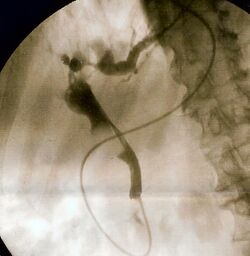

Fluoroscopic image of common bile duct

- To undergo ERCP for diagnosing diseases of biliary tree or their management

- Endoscopic retrograde cholangiopancreatography (ERCP)

- Transhepatic pancreato-cholangiography (TPC)